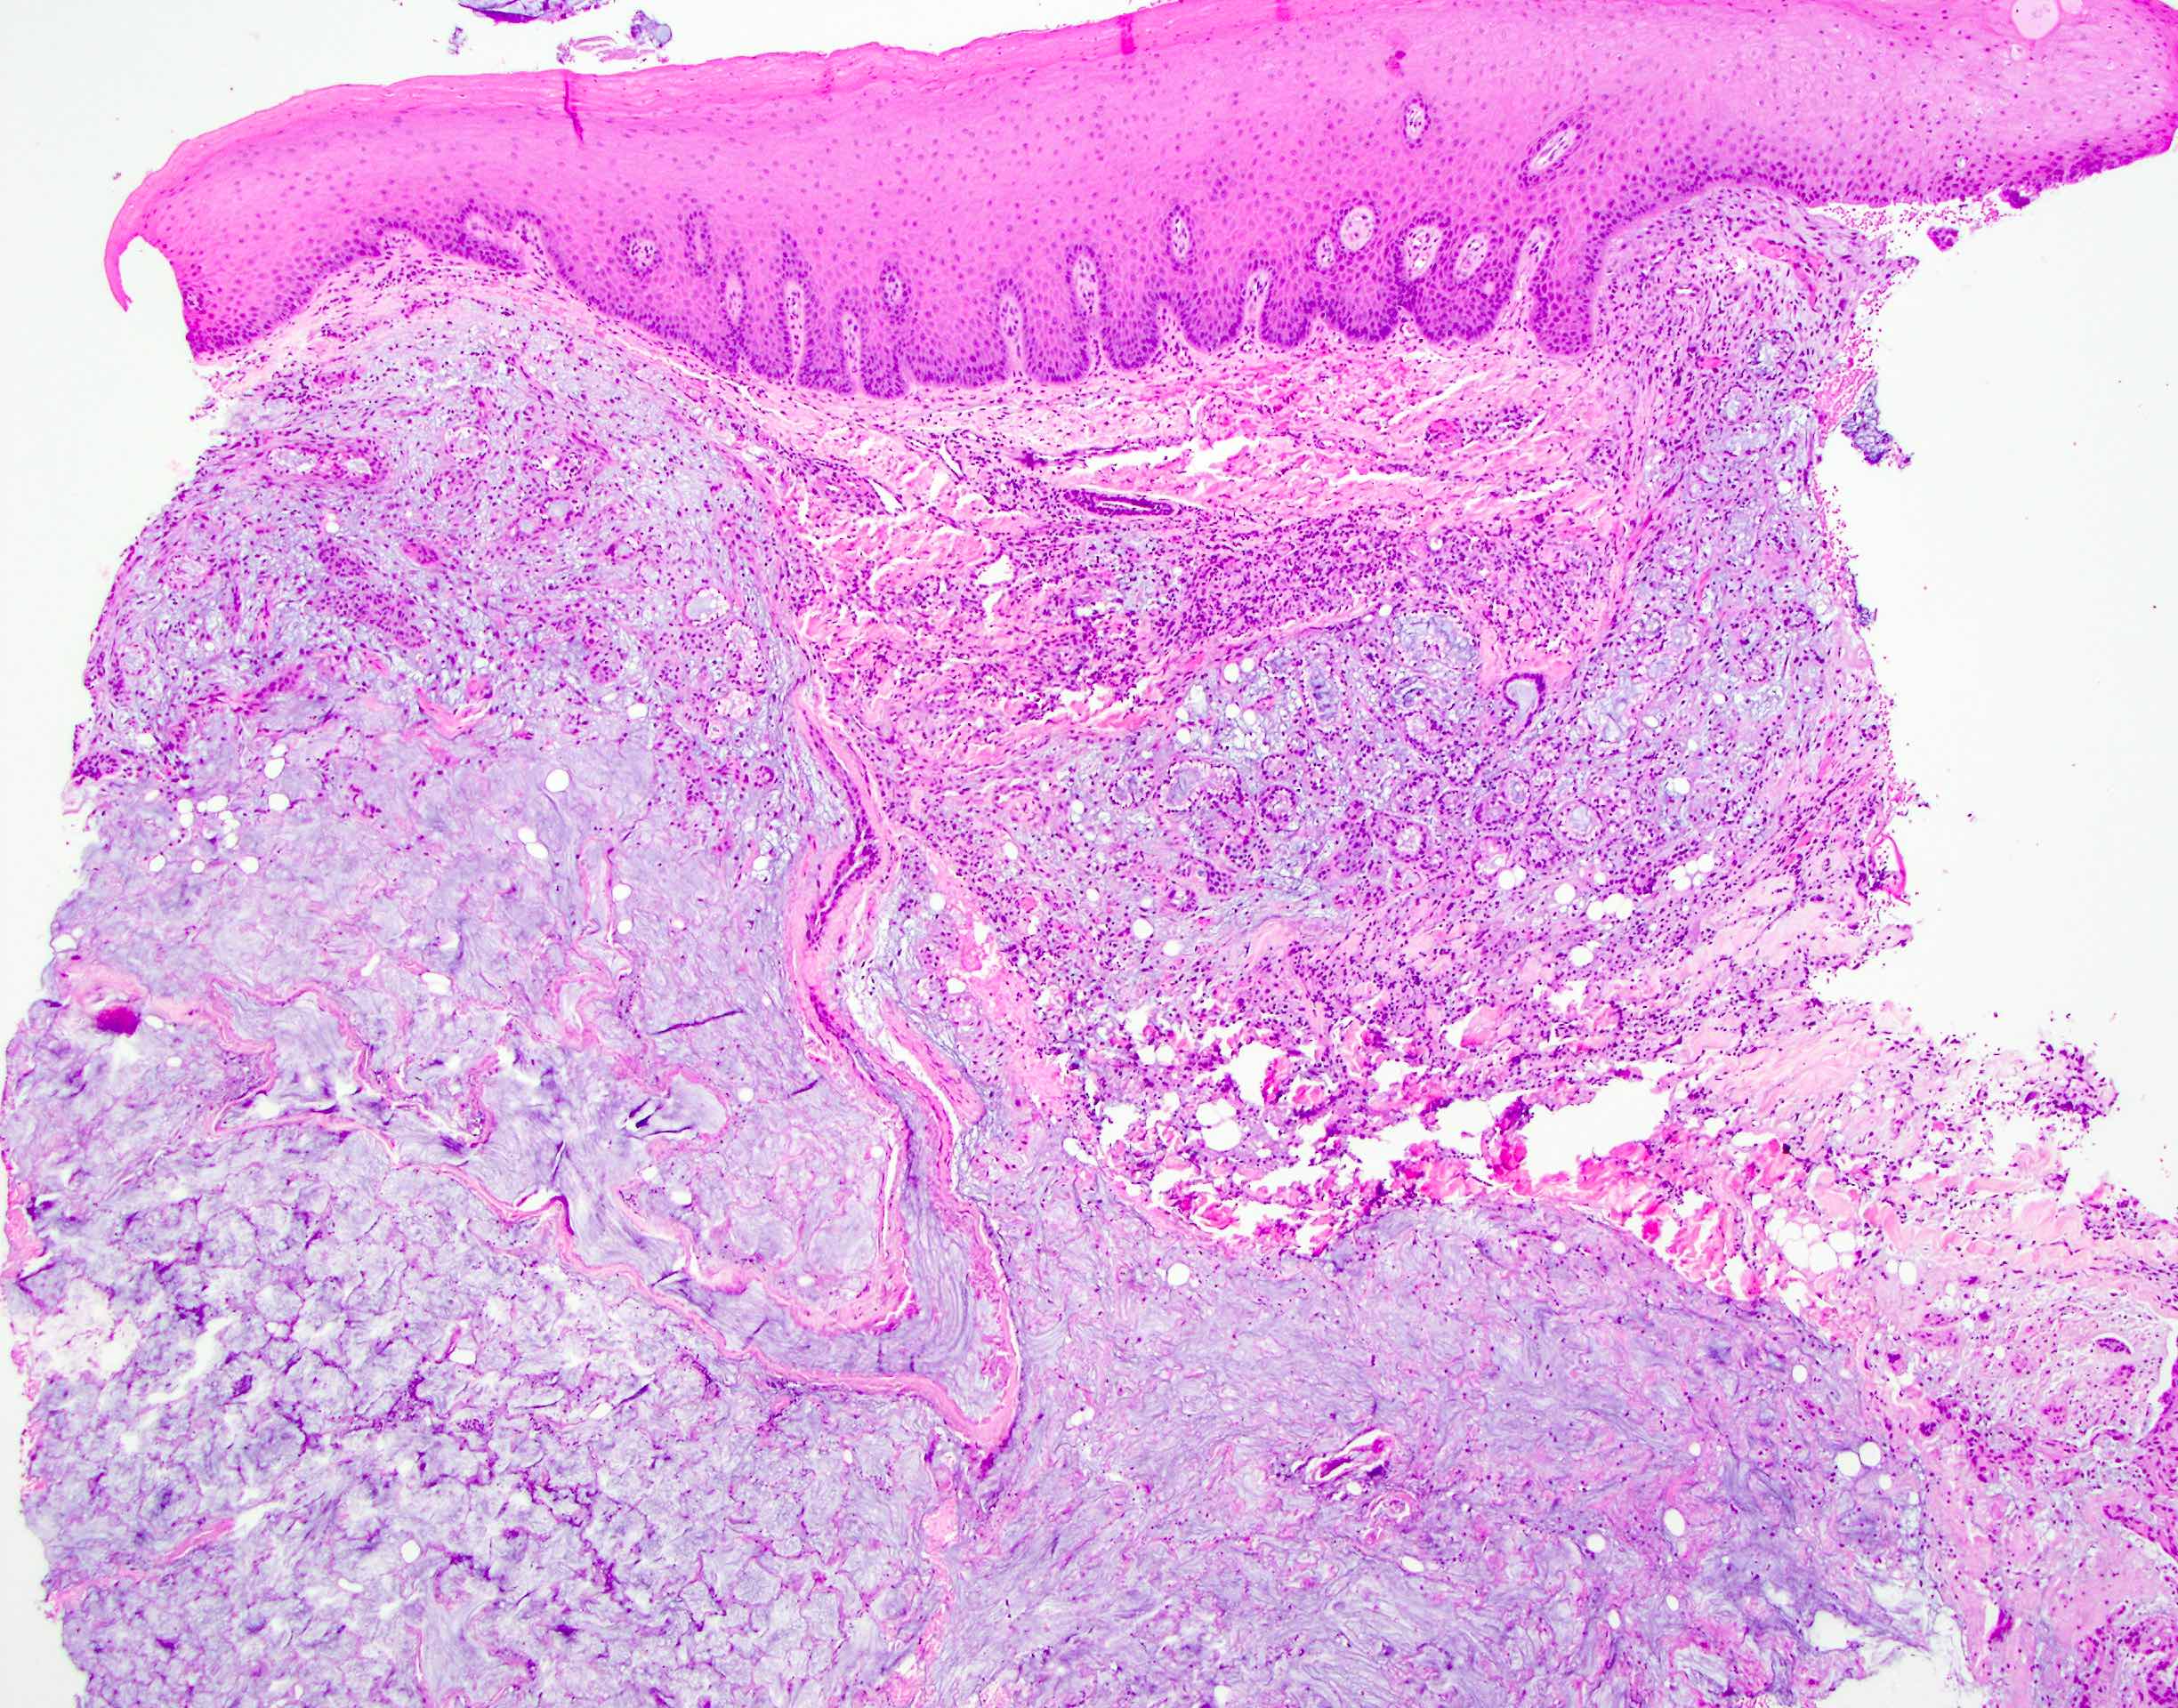

Microscopic (histologic) description

- Squamous metaplasia of ductal structures and acini with preservation of the salivary lobular architecture is an essential feature, according to World Health Organization (see WHO classification-oral cavity & oropharynx)

- Necrosis / infarction of acini characterized by loss of nuclei and cell borders with or without zones of spilled mucin

- Pseudoepitheliomatous hyperplasia with generally bland cytology or keratinocytic regenerative atypia

- Reactive, myxocollagenous background stroma

- Surface ulceration, granulation tissue and subacute inflammation may be present

- Has been conceptualized by 5 histologic stages of development and evolution: infarction, sequestration, ulceration, repair and healing (Int J Oral Surg 1982;11:283)

Microscopic (histologic) images